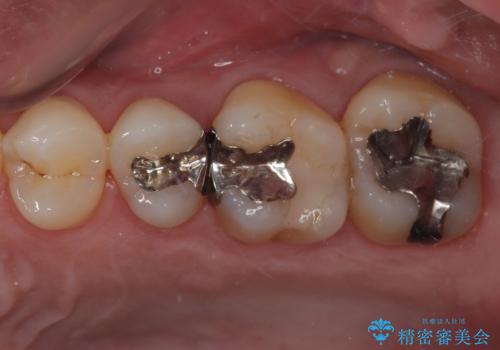

理想的な咬み合わせに改善した上で、インプラント補綴治療を行うこととしました。

部分矯正を行ったこと治療期間は長くなりましたが、違和感のない咬み合わせを達成することができました。